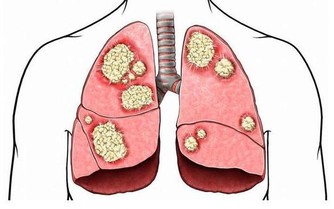

患有4期膀胱癌意味著什麼?第4階段是癌症的最晚期階段。在這個階段,癌細胞通常會擴散到疾病的原始位置以外的其他器官。

當膀胱癌到達第4階段時,原始腫瘤經常生長並推動膀胱壁。癌細胞可能已經擴散到靠近膀胱的器官或更遠的器官,例如肝臟或肺部。於是其症狀可能包括: